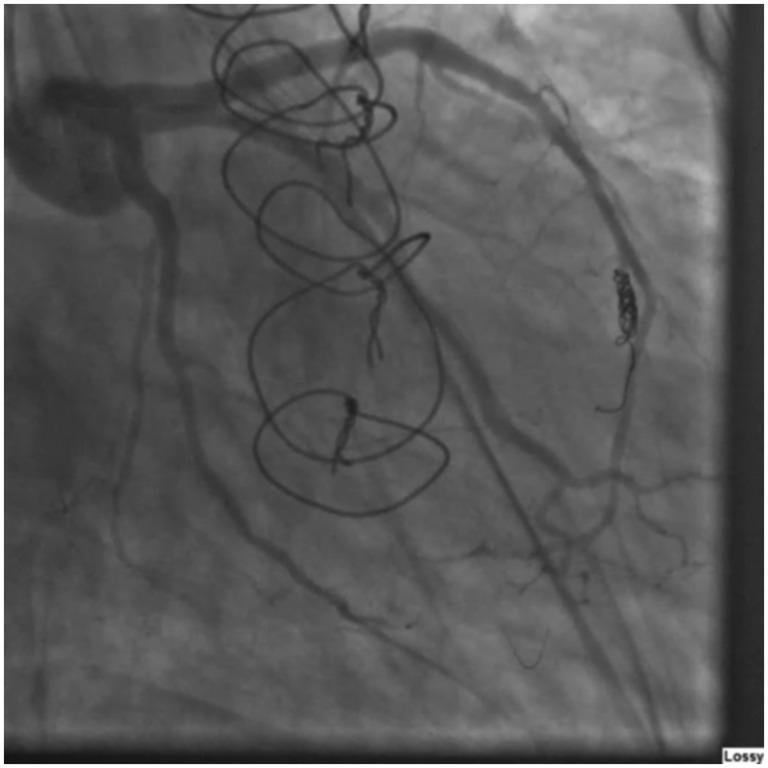

A coronary cameral fistula treated with coil embolization.

A 56-year-old man who had twice previously undergone orthotopic heart transplantation was admitted with dyspnea and heart failure symptoms. A biopsy excluded rejection. Left heart catheterization revealed a coronary cameral fistula. After the patient was given mild diuretics, his condition improved. No significant fistula flow was detected, and he was discharged. Several months later, the patient was readmitted with worsening chest pain and dyspnea. Left ventricular end-diastolic pressure and flow through the fistula were increased. To correct the coronary cameral fistula, we performed a coil embolization without complications. Several months later at follow-up, the patient's symptoms had resolved, and his left ventricular end-diastolic pressure had normalized. We conclude that coronary fistulas may be caused by trauma to the heart during the de-airing process, which may be prevented in the future with the development of safer and more effective de-airing techniques.